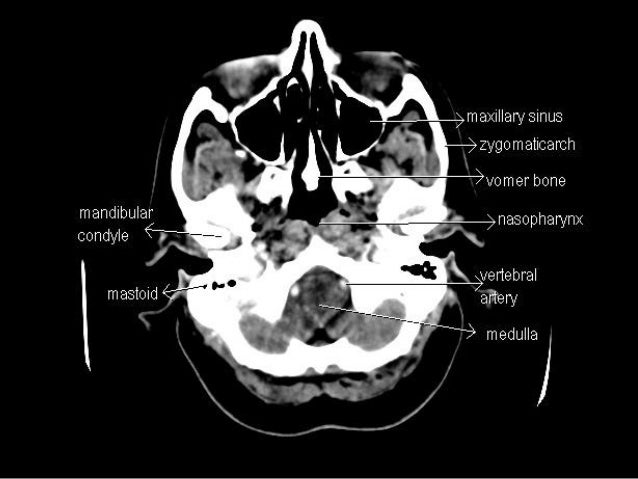

Sectional anatomy of the structures of the brain as viewed with ct mri and pet fusion imaging. It is superior to the upper pole of the right kidney whereas the left adrenal gland is anteromedial to the upper pole of the left kidney.

These labeling exercises are to aid the viewer in learning the sectional anatomy of the brain.

The cross sectional anatomy of the normal adrenal gland is identical on ct and mri. This mri brain cross sectional anatomy tool is absolutely free to use. Choose from 500 different sets of cross sectional anatomy brain flashcards on quizlet.

Mri of the brain. Anatomy of the encephalon mri in axial slices we created a brain atlas that is an interactive tool for studying the conventional anatomy of the normal brain based on a magnetic resonance imaging exam of the axial brain. Use the mouse scroll wheel to move the images up and down alternatively use the tiny arrows on both side of the image to move the images on both side of the image to move the images.